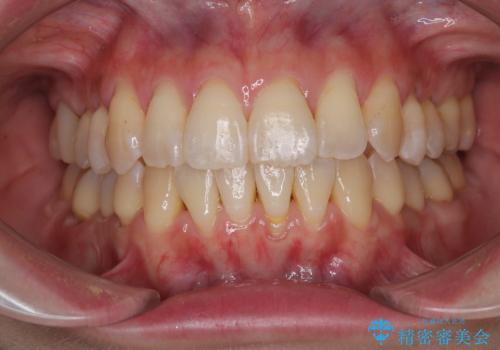

前歯のデコボコをインビザラインで目立たずに改善

- 上下前歯のデコボコを気にして来院された患者様です。

デコボコは顕著であるものの、口元の突出感は強くないため、非抜歯にて矯正治療を行うこととしました。

装置はワイヤー装置でもマウスピースでも対応可能でしたが、より目立たない装置をご希望とのことで、インビザラインにて矯正治療を行うこととしました。

元々の叢生と歯肉退縮傾向になる歯肉であったため、ブラックトライアングルが目立つことが想定されました。

治療過程でブラックトライアングル改善のため、IPR(歯と歯の間を削る)を活用しました。